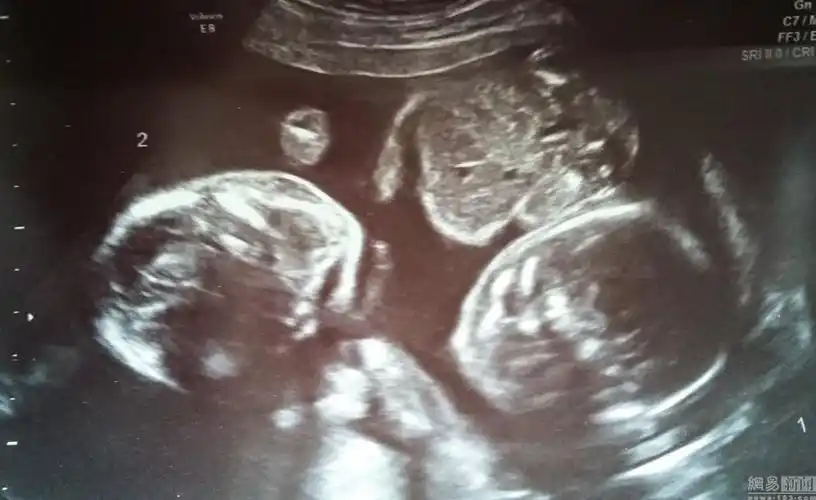

b超显示路易斯怀上了双胞胎